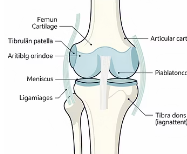

3. 반월상연골 손상

무릎 관절 안에 있는 연골판이 손상되면 염증 반응이 나타납니다.

무릎이 잠기는 느낌이나 특정 각도에서 통증이 심해지는 경우가 많습니다.

4. 인대 손상

십자인대나 측부인대 손상 후 무릎에 물이 차는 경우도 흔합니다.

외상 이후 갑자기 무릎이 붓고 통증이 심해지는 것이 특징입니다.